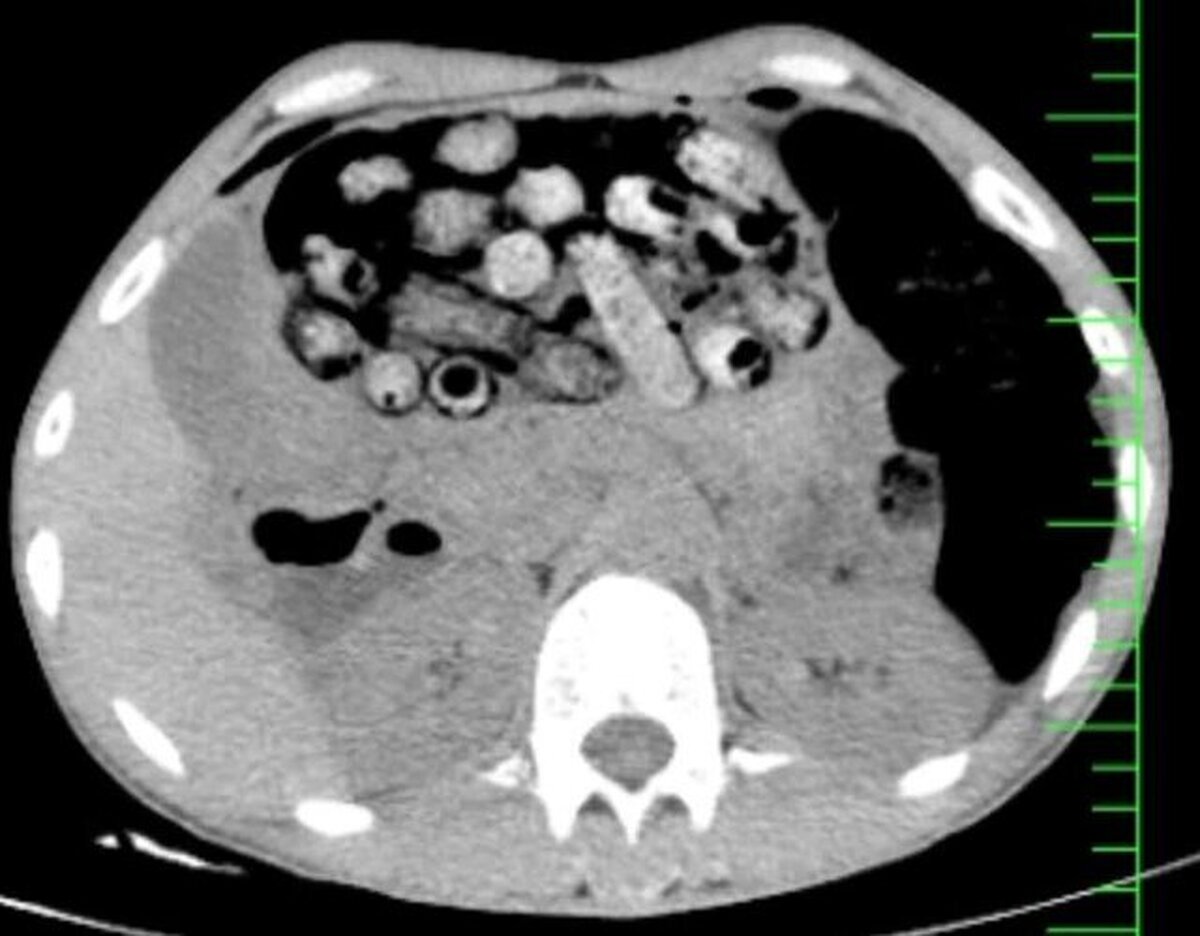

براساس اطلاعات اولیه مأمور همراه، بیمار پیش از مراجعه، اقدام به بلع تعدادی بسته محتوی مواد مخدر کرده بود. در پی انجام تصویربرداری فوری، تعداد زیادی بسته مشکوک در معده و روده کوچک و بزرگ وی مشاهده شد.

به نوشته ایسنا، با توجه به خطر بالای پارگی احتمالی بستهها و بروز عوارض تهدیدکننده حیات، بیمار بلافاصله به اتاق عمل منتقل شد و جراحی سنگین وی از ساعت سه بامداد آغاز شد.

در این جراحی که به سرپرستی دکتر سامان شیخی، عضو هیأت علمی گروه جراحی عمومی دانشگاه علوم پزشکی البرز و با همکاری تیمهای اورژانس، تصویربرداری، بیهوشی و جراحی انجام و ۹۰ بسته از معده و روده بیمار خارج شد.